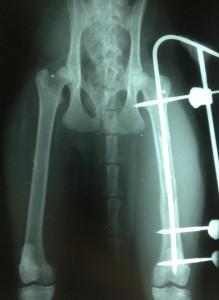

Največkrat svetujemo stabilizacijo s kirurškimi tehnikami (eksterni fiksacijski sistem, intramedularne in Kirschnerjeve igle, mini ploščice in vijaki), včasih pa je ta neizbežna. Največ uporabljamo tako imenovani eksterni fiksacijski sistem, ki omogoča kakovostno, čvrsto stabilizacijo, hitrejše zdravljenje in seveda tudi dobro prognozo (Slika 4). Za takšne posege so potrebni, kot že rečeno, dodatna usposobljenost, oprema in dobro usposobljen kader, ki se redno izobražuje.